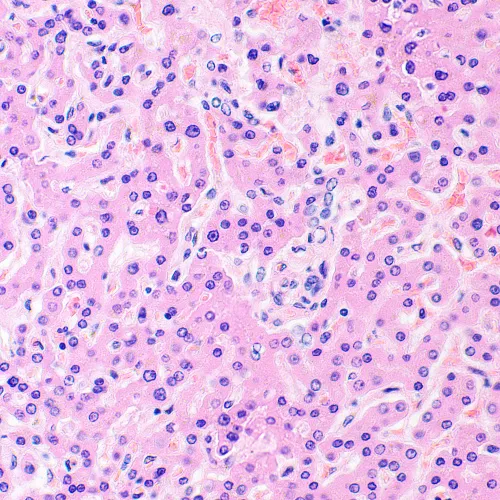

Изследователски клас микроскоп. Конструиран за наблюдение на прозрачни и полупрозрачни биологични проби, като например натривки и напречни сечения в преминаваща светлина по метода на светлото поле. Монтирането на допълнителни принадлежности ще осигури възможност за използване на методите на тъмното поле, фазовия контраст, диференциалния интерферентен контраст, флуоресценцията и поляризацията.

Микроскопът е подходящ за микробиологичен анализ, медицински диагностики и решаване на научни и изследователски проблеми.

Фазовоконтрастни устройства, флуоресцентно приспособление, кондензери за тъмно поле, устройства за поляризация и DIC устройства увеличават контрастните методи и позволяват изучаването на обекти, невидими в светлото поле.

- Наблюдение на прозрачни и полупрозрачни образци по метода на светлото поле с пропусната светлина